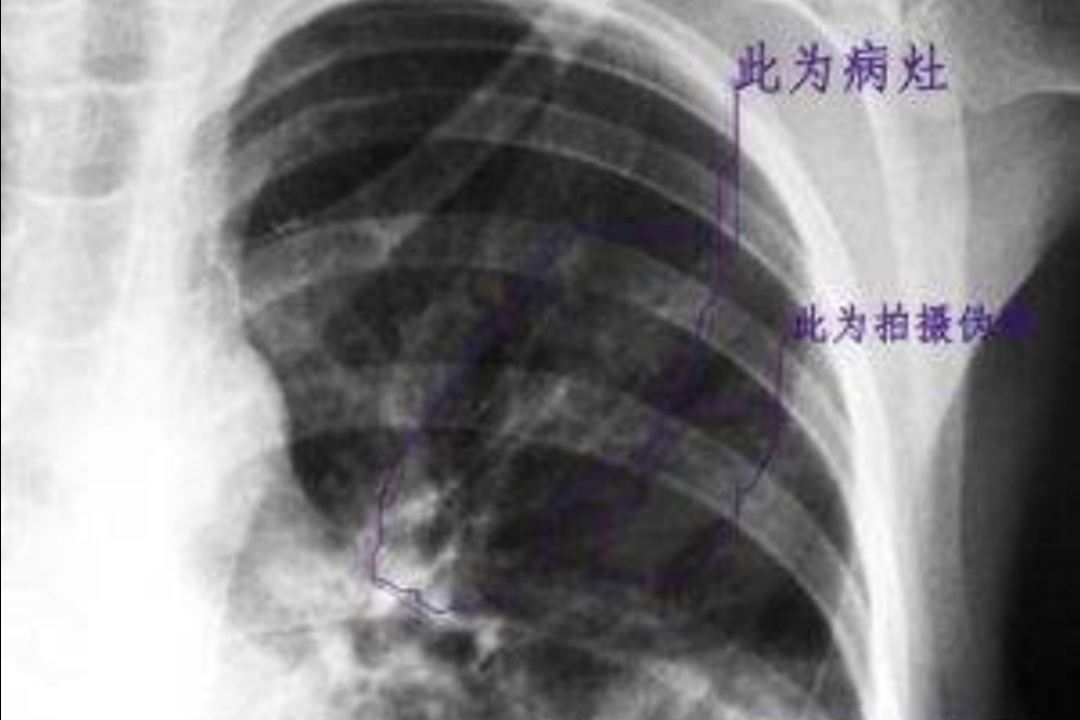

⑥肺部体征与症状以及影像学表现不一致是肺炎支原体肺炎的特征。